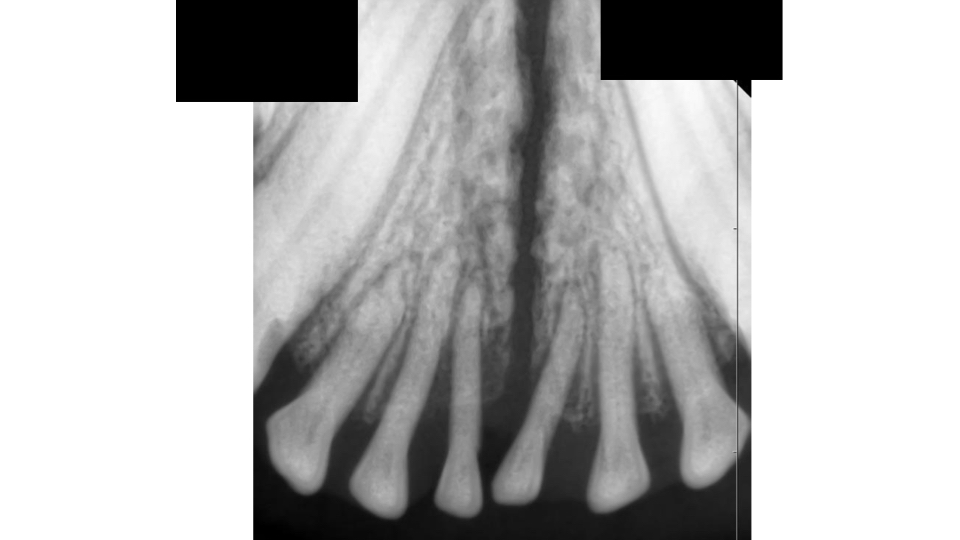

こちらの写真の症例の子は健康診断でいらした際に下の歯がグラグラしているのを発見しました。

肉眼的にも歯肉が後退しているのが分かります。

歯科用レントゲンでは歯を支える歯槽骨が歯周病によって退行していることが確認できました。

最初の写真に比べると切歯の背が高くなったように見えますが、これは後退した歯槽骨に合わせて切開した歯肉を縫合しているためです。

切歯同士の隙間が開くことで新たな歯垢の付着を最小限に、かつ歯ブラシや歯間ブラシで磨きやすくしています。